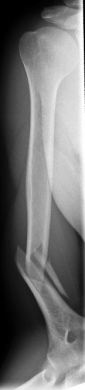

Picture: Here you can see a completely shifted upper arm fracture with a strong bend of the axis. First the operative treatment was performed by repositioning the bone and internal splinting of the fracture with a medullary nail.